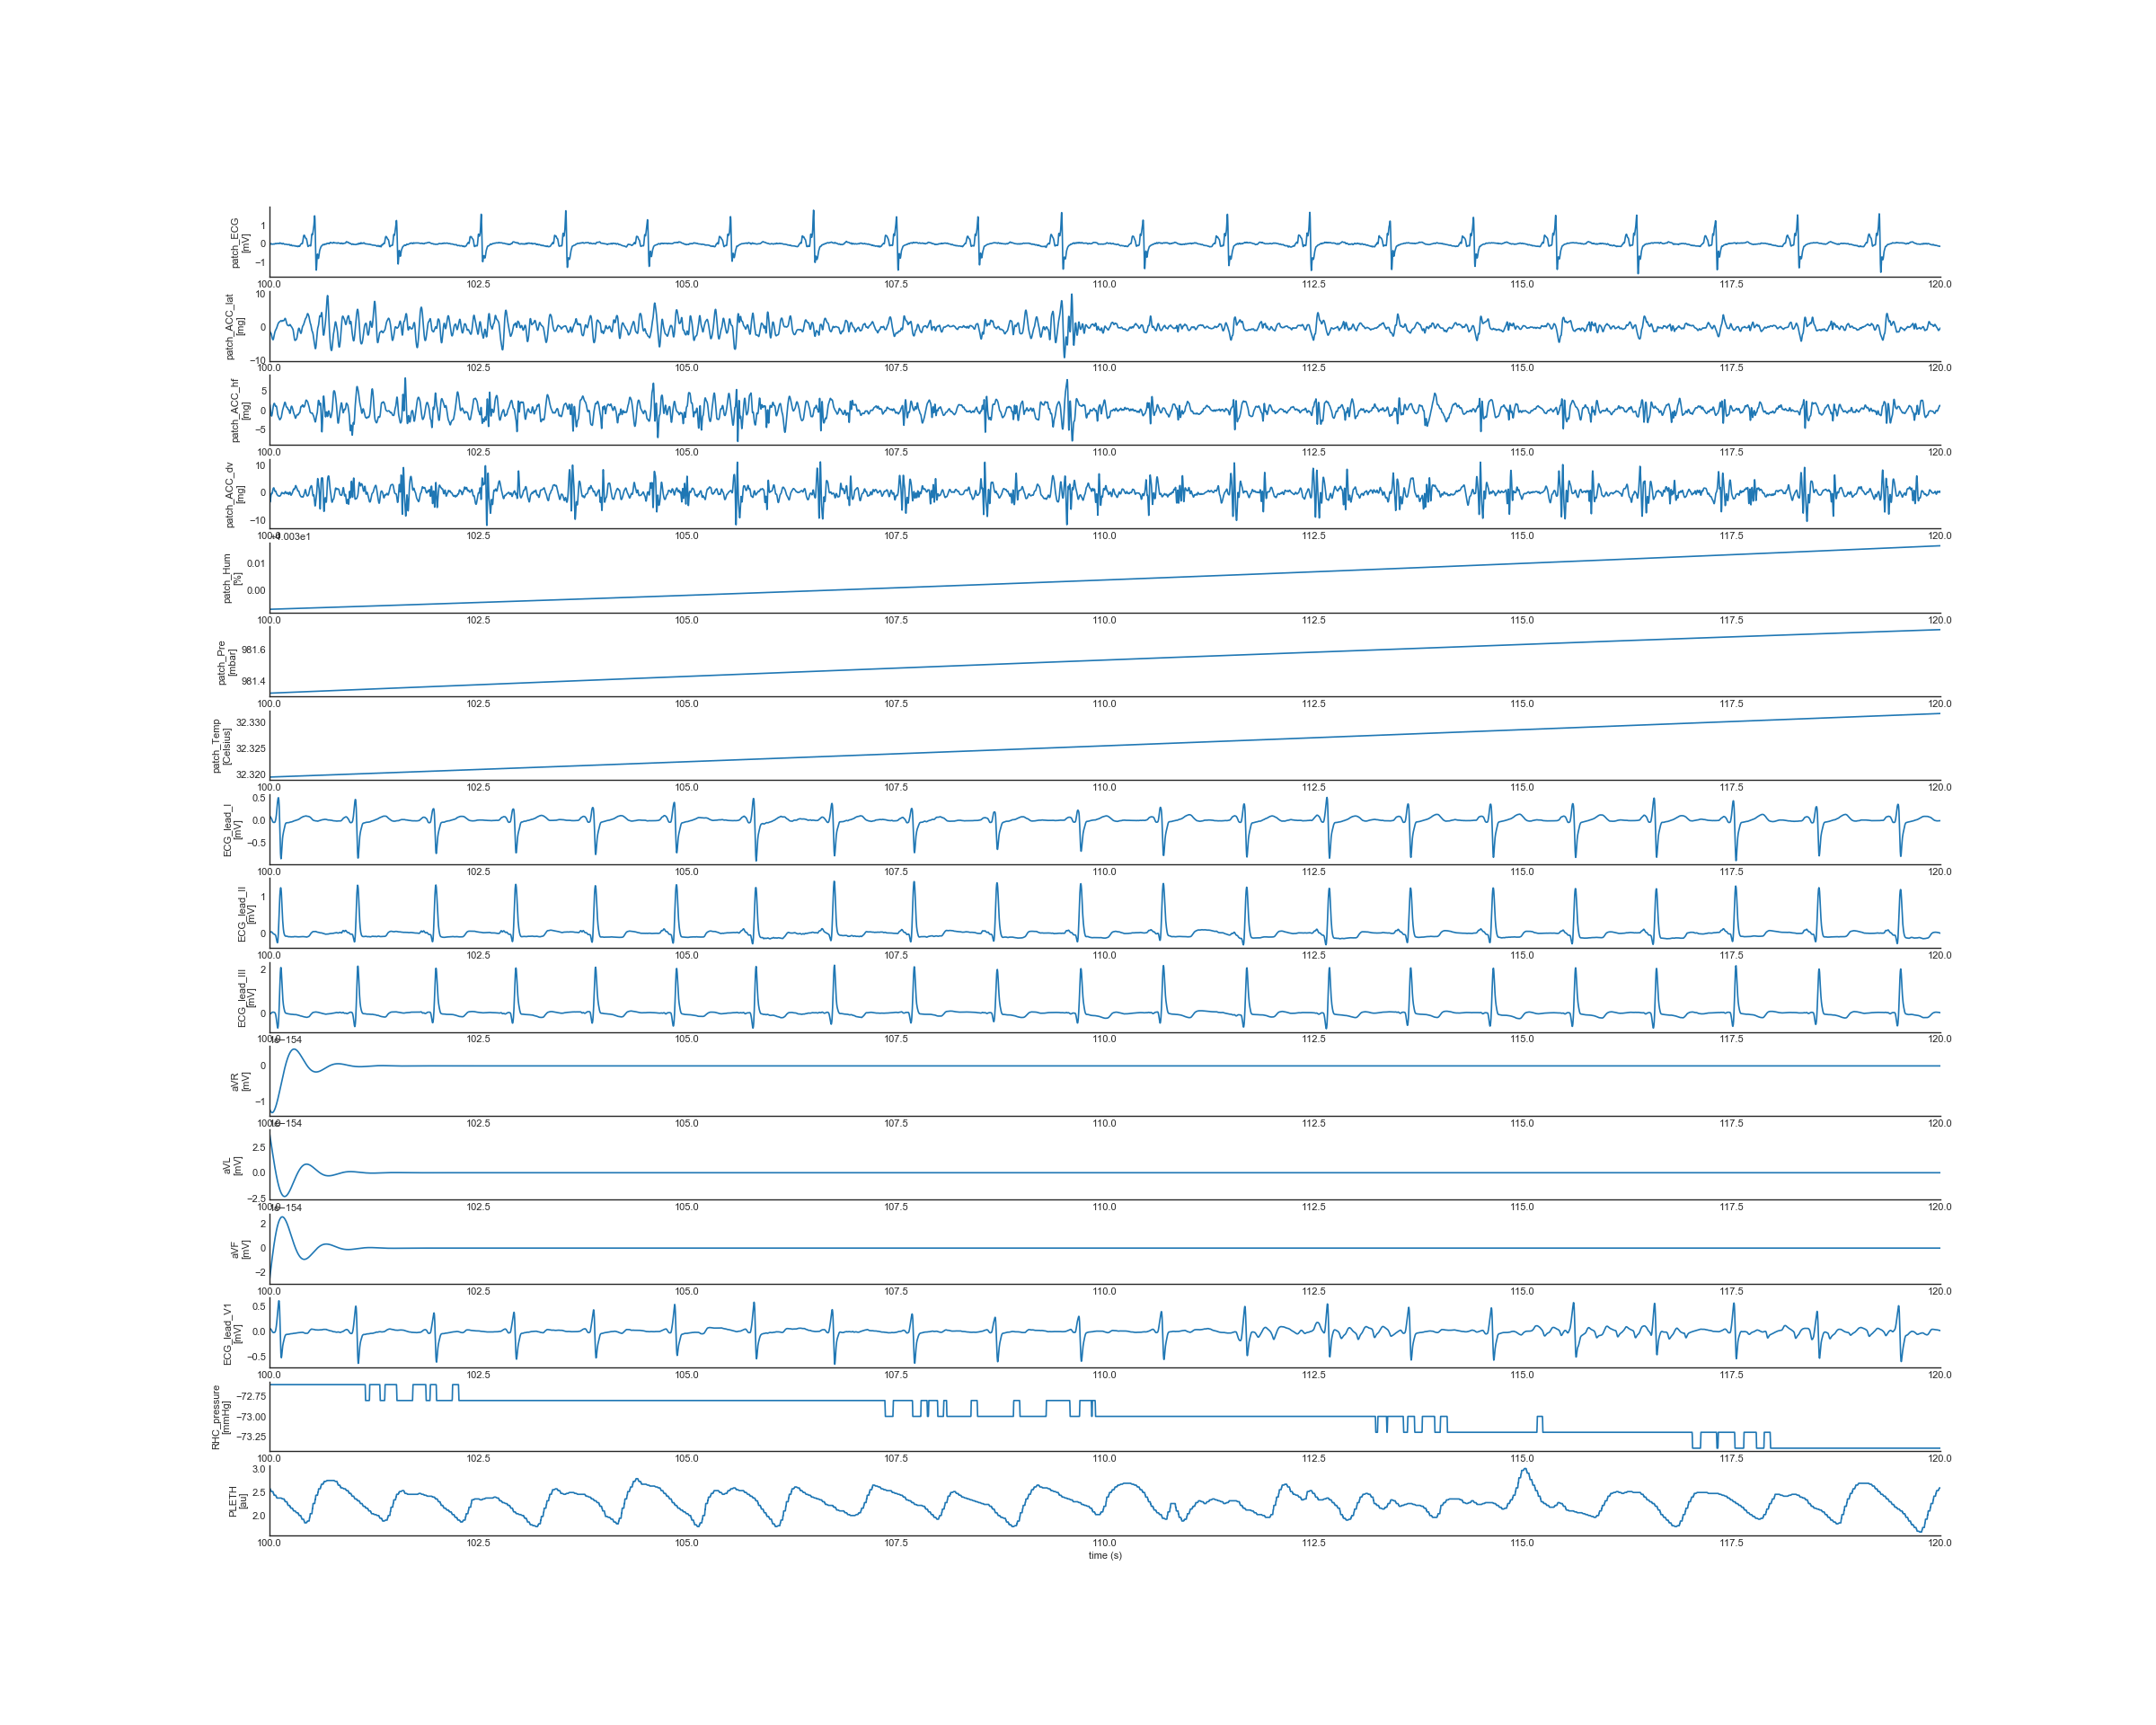

Contents in signal preview

In this folder, plots are provided to help users quickly preview the quality of the data are provided. Three different windows of the WFDB signals are plotted for all subjects:

• /FirstChamber_20s: shows the WFDB signals 5s before and 15s when RHC first entered a chamber.

• /full: shows the full recording of the WFDB signals

• /random_20s: shows a randomly selected 20s window of the WFDB signals

Signals in the dataset recorded by the wearable patch (stored in the WFDB format: TRMXXX-RHCY.dat)

• Patch_ECG: ECG signal measured by the patch (unit: mV)

• Patch_ACC_lat: ACC signal in the lateral direction measured by the patch (unit: mg)

• Patch_ACC_hf: ACC signal in the head-to-foot direction measured by the patch (unit: mg)

• Patch_ACC_dv: ACC signal in the dorsal-ventral direction measured by the patch (unit: mg)

• Patch_Hum: Humidity signal measured by the patch (unit: %)

• Patch_Pre: Ambient pressure measured by the patch (unit: mbar)

• Patch_Temp: Skin temperature measured by the patch (unit: Celsius)

Signals in the dataset recorded by Mac-Lab (also stored in the same WFDB file: TRMXXX-RHCY.dat)

• RHC_pressure: RHC blood pressure recorded by Mac-Lab (unit: mmHg)

• ART: Arterial blood pressure recorded by Mac-Lab using arterial line (unit: mmHg)

• ECG_lead_I: Lead I ECG recorded by Mac-Lab (unit: mV)

• ECG_lead_II: Lead II ECG recorded by Mac-Lab (unit: mV)

• ECG_lead_III: Lead III ECG recorded by Mac-Lab (unit: mV)

• aVR: Augmented Vector Right ECG recorded by Mac-Lab (unit: mV)

• aVL: Augmented Vector Left ECG recorded by Mac-Lab (unit: mV)

• aVF: Augmented Vector Foot ECG recorded by Mac-Lab (unit: mV)

• ECG_lead_V1: V1 pericordial lead ECG recorded by Mac-Lab (unit: mV)

• PLETH: Plethysmogram signal recorded by Mac-Lab using pulse oximeter sensor (unit: a.u.)

• RESP: Respiratory signal recorded by Mac-Lab (unit: a.u.)